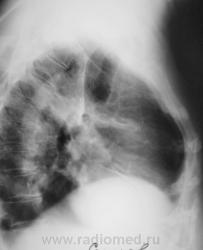

Произведена стандартная рентгенография.

Боковая проекция.

А не ателектаз S3? И легкое уменьшено, и высока междолевка, и в корне что-то?

Вот, вот и я о том же - в корне-то кругляк.

Верхняя доля уменьшена в объёме, средняя, вроде-бы увеличена в объёме?

Гомогенное затенение в пределах сегмента, в форме треугольника, основанием прилегающего к плевре, вершиной обращённого к корню; высокое стояние купола диафрагмы на стороне поражения; полнокровие корней лёгких --- разве нет? При определённой клинической картине было бы весьма показательно, при отсутствии её --- сомнительно.

с учетом давности заболевания можно предположить развитие фиброза на месте инфаркта при тэла. высокий правый купол диафрагмы, явления застоя, расширенные корни, бронхо-сосудистая дорожкак корню для тэла также характерны. может помочь сцинтиграфия.

Верхняя доля правого лёгкого бесспорно уменьшена. Но вот корень… картина не похожа на центральный рак. А на инфаркт-пневмонию не похожа клиника. Возможно будет результат КТ.